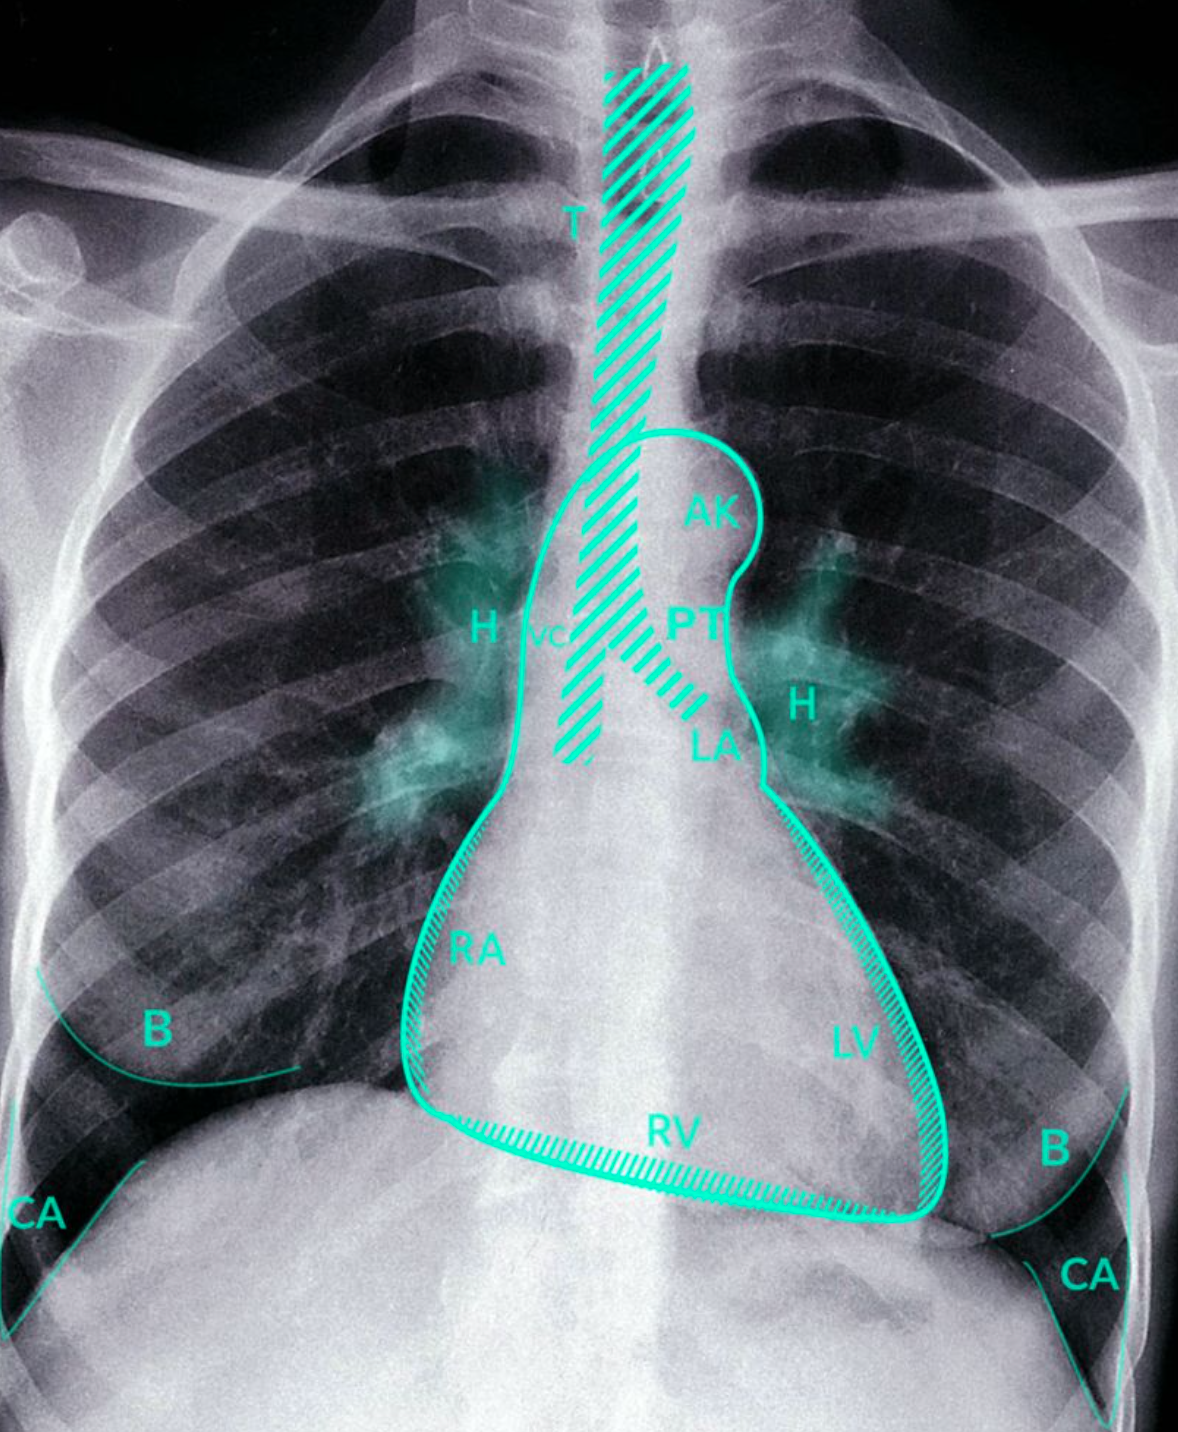

Normal chest finding on a Rx PA ?